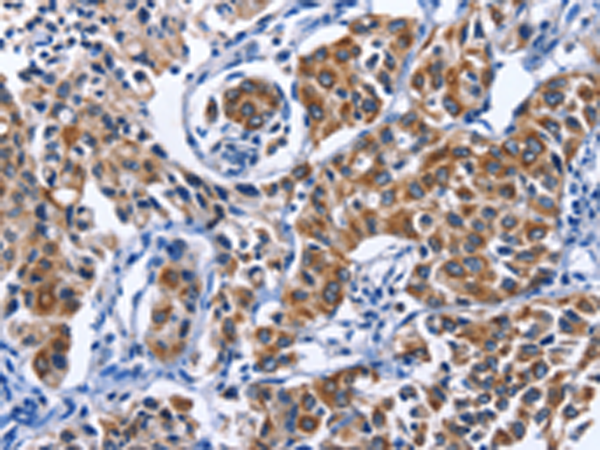

分类: 科研抗体货号: P07452别名: ME; HME; MME; MMP-12应用: WB,IHC反应种属: Human